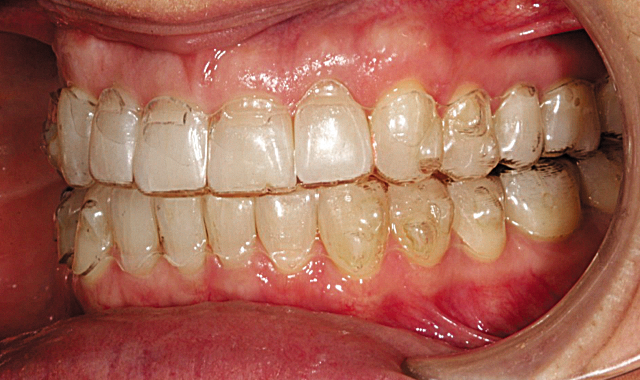

This patient presented with concerns over the esthetics of her smile due to the shifting of her teeth over time (Figs. 1-3). We diagnosed crowding and asymmetry of her teeth and gingival tissues. Our treatment plan included Invisalign treatment, occlusal equilibration after orthodontics and Vivera retainers.

Fig. 2

Fig. 3